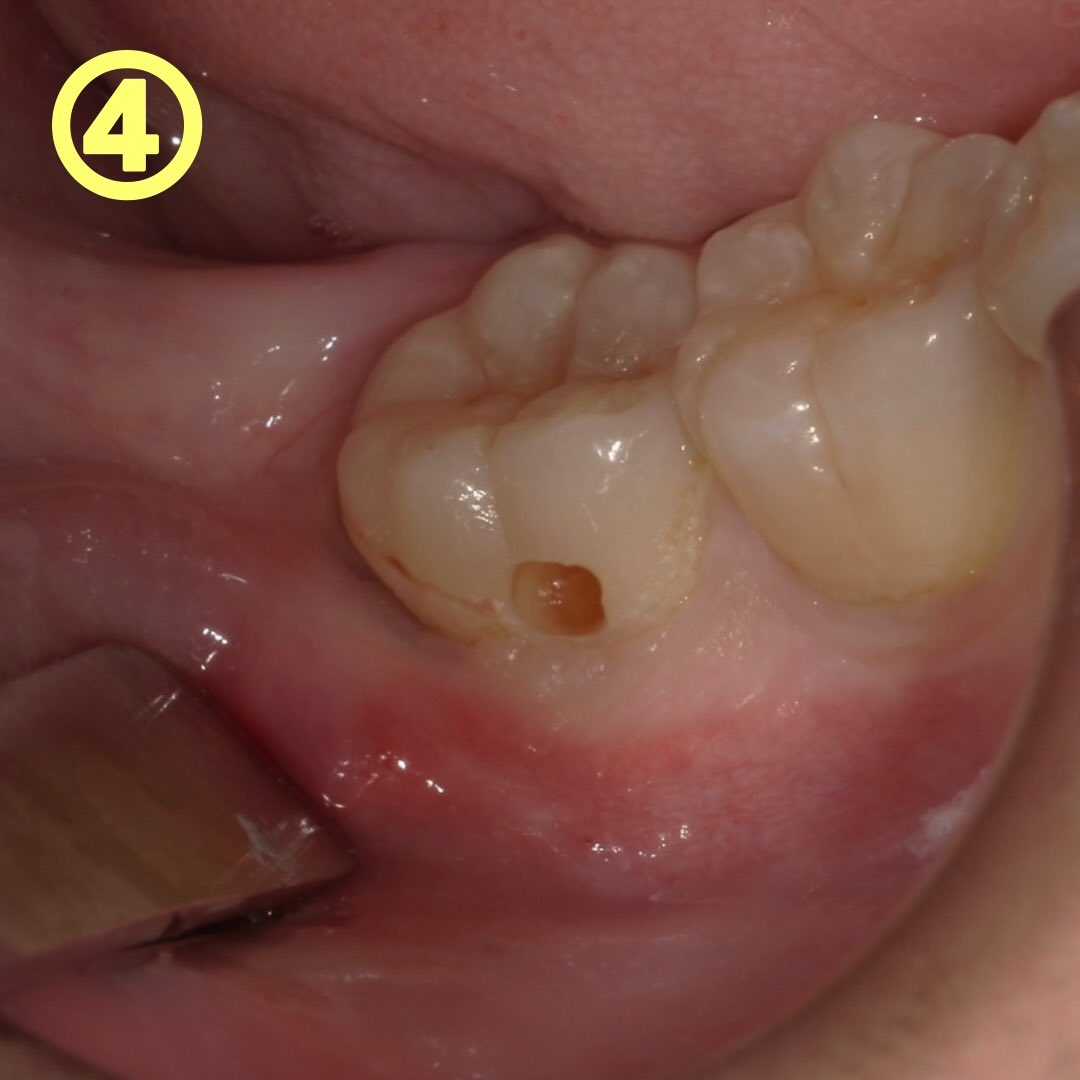

青い色が残っている為再度切削を行いました→写真④

切削して染め出しを数回繰り返し、色がほとんど付かなくなった所で穴を埋める作業を行います(充填と言います)